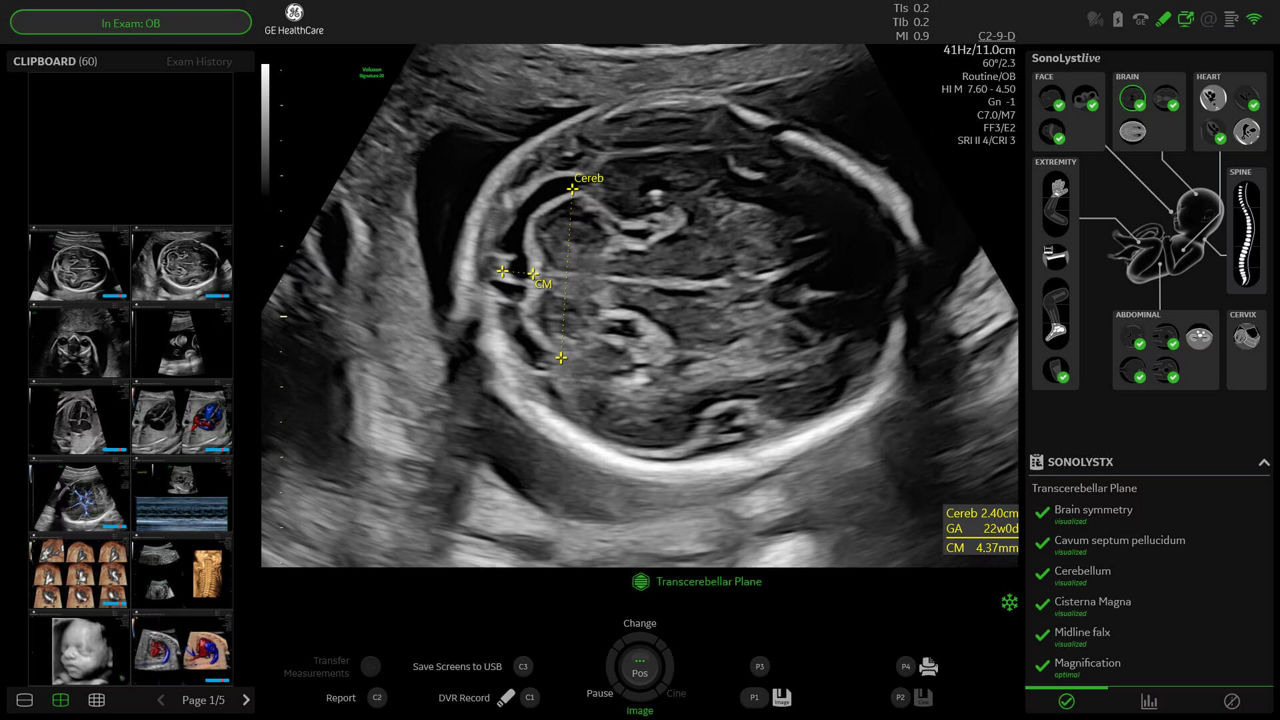

Standard ISUOG 2nd trimester exam 40% faster with SonoLyst

Complete 20-week exams in 65% less keystrokes with SonoLyst